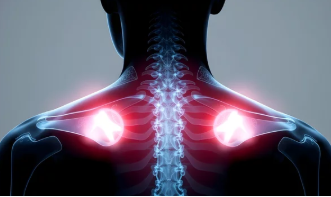

어깨 석회화 건염은 어깨 힘줄(건)에 칼슘이 축적되어 석회질이 형성되고, 이로 인해 통증과 염증이 발생하는 상태를 말합니다.

- 주로 회전근개(어깨 관절을 안정시키는 근육군) 힘줄에서 발생

- 극상근 건(어깨 위쪽 힘줄)에 가장 흔히 발생